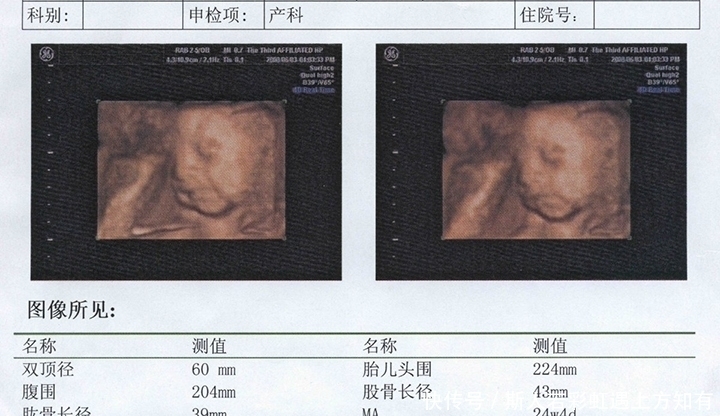

第一次孕检要检查的项目比较多,它主要是对孕妇做一个全面的检查,包括孕妇的基本信息,比如:生育史、以前是否患过重大疾病、家庭情况等。除血常规、尿常规、尿碘、甲功等检查之外,还需要做B超、胎儿的NT检查。

腹部B超单